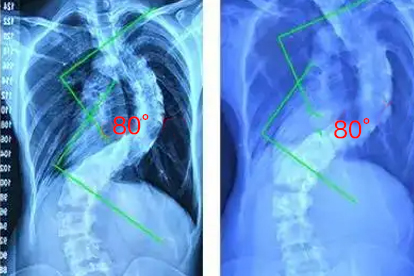

四川省人民医院骨科是省内重点专科,在脊椎疾病的诊疗方面具有较强实力。医院引进了国际的脊椎微创手术系统,能够开展椎间孔镜、椎体成形等微创手术。医疗团队在脊椎退变性疾病、脊椎侧弯矫正等方面具有丰富的临床经验。